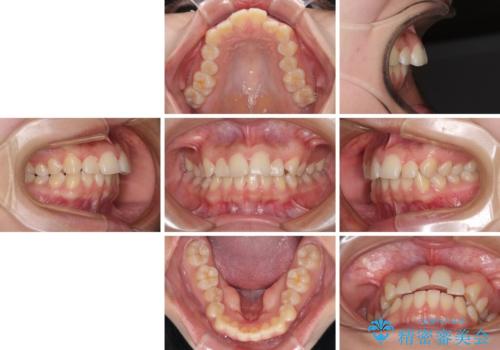

- 前歯の叢生を気にして来院された患者様です。

奥歯の咬み合わせを見ると、上顎が下顎に対して相対的に前方にあり、上下の前歯が接触していない状態でした。

咬み合わせを改善するためには、上顎臼歯を後方に移動させた咬み合わせにする必要があります。

インビザライン単体で改善することも可能ですが、咬合力が強く、単位で達成する可能性が低いと考えられたため、カリエール・ディスタライザーという補助装置を併用して、より確実性を上げることとしました。

奥歯の咬み合わせを改善しながら、並行してインビザラインで歯列を整えることとしました。